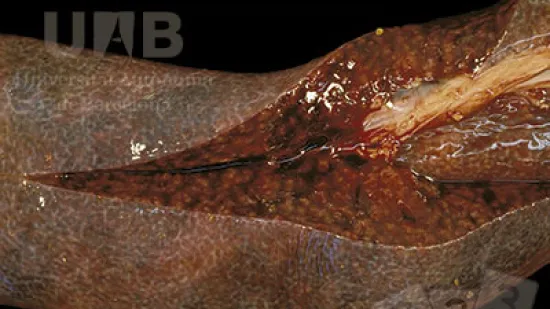

Semaine du 16-Aoû-2021

Quelle lésion peut-on observer sur cette carcasse ?